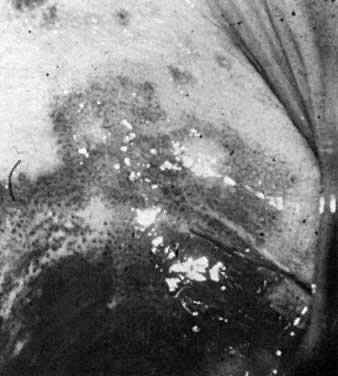

Fig. 5. Microscopic fields from single large urethral caruncle. A. Papillomatous changes. B. Granulomatous changes. C. Angiomatous changes. D. Adenomatous changes.